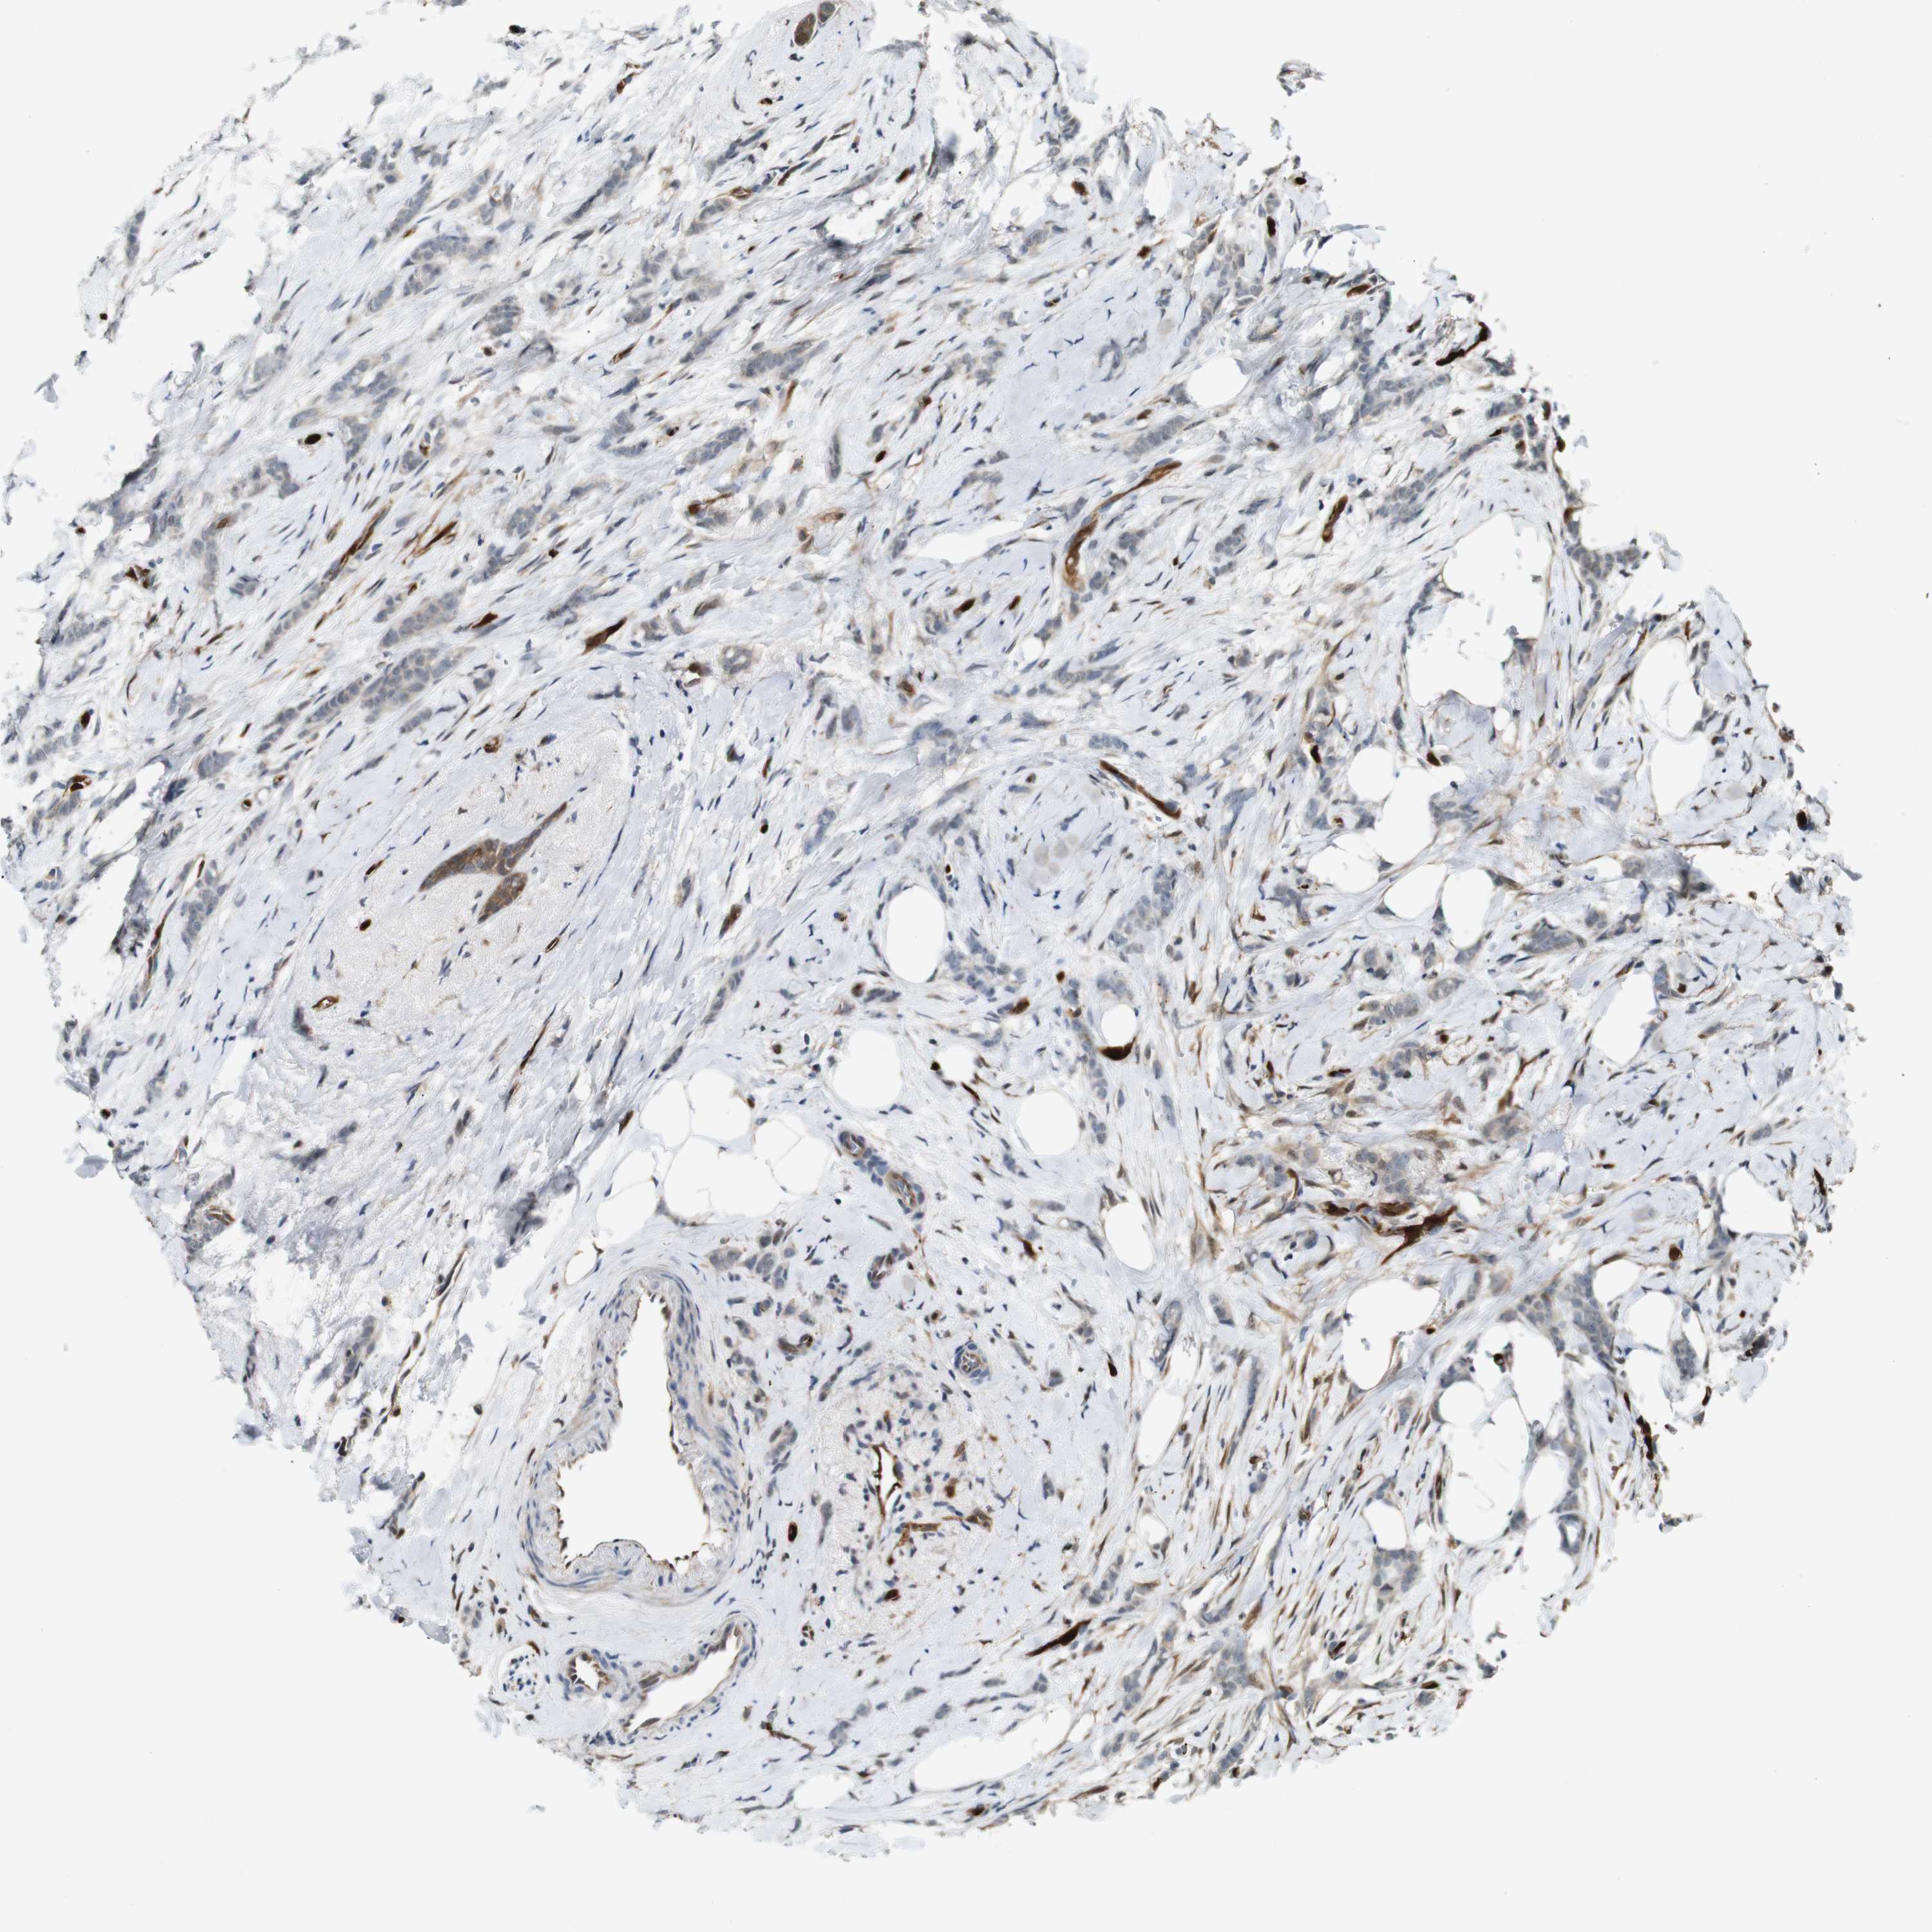

CANCER BREAST CANCER Show tissue menu

BRCA TCGA BRCA VALIDATION PROTEIN EXPRESSION